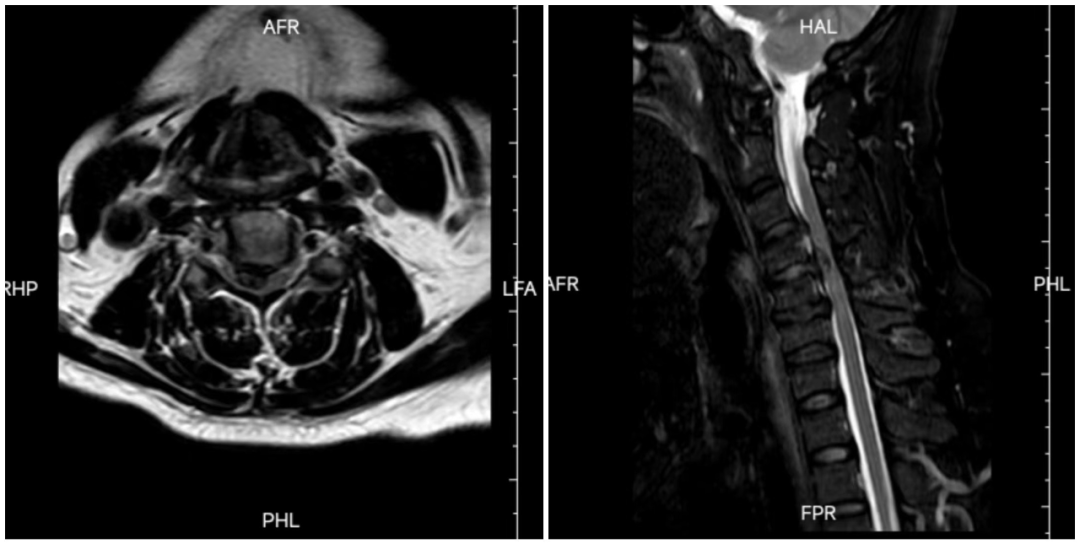

影像学检查显示,三个节段椎间盘突出,骨质增生压迫脊髓,手术风险极高。以往多采取相对安全的颈椎后路手术,但创伤较大,且无法直接去除致压物;前路手术以往多采取切除椎体的方式,虽然相对安全,但是同样存在着创伤大的弊端。

经吕世桥主任团队术前讨论,认为压迫主要集中在三个椎间盘水平,且主要是大块软性压迫,可以采用更为微创的前路三节段间盘切除椎间融合固定术。手术由吕世桥主任主刀,通过颈椎前方3cm的小切口,顺利切除压迫脊髓的三节段椎间盘。术后,患者的肢体麻木、无力症状得以即刻缓解,手术效果立竿见影。